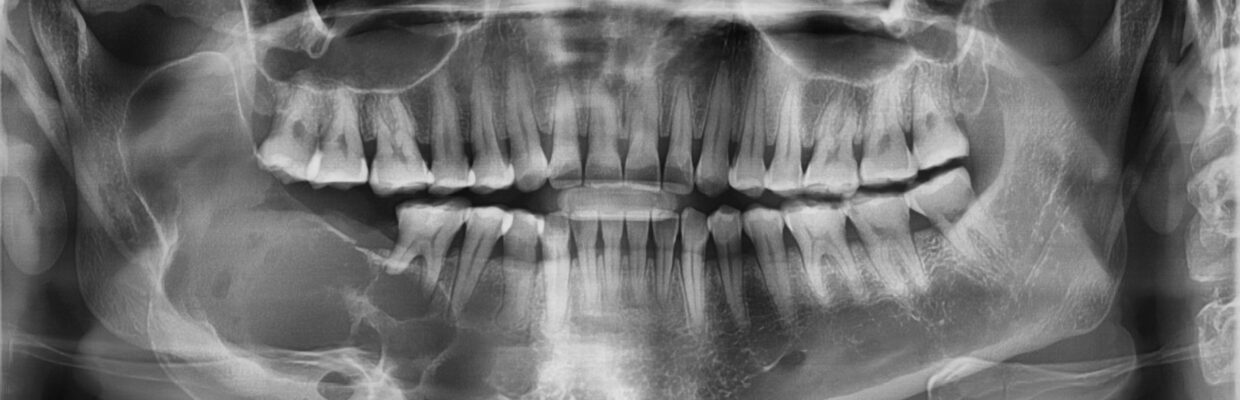

Patient information – Surgical removal of teethContact us